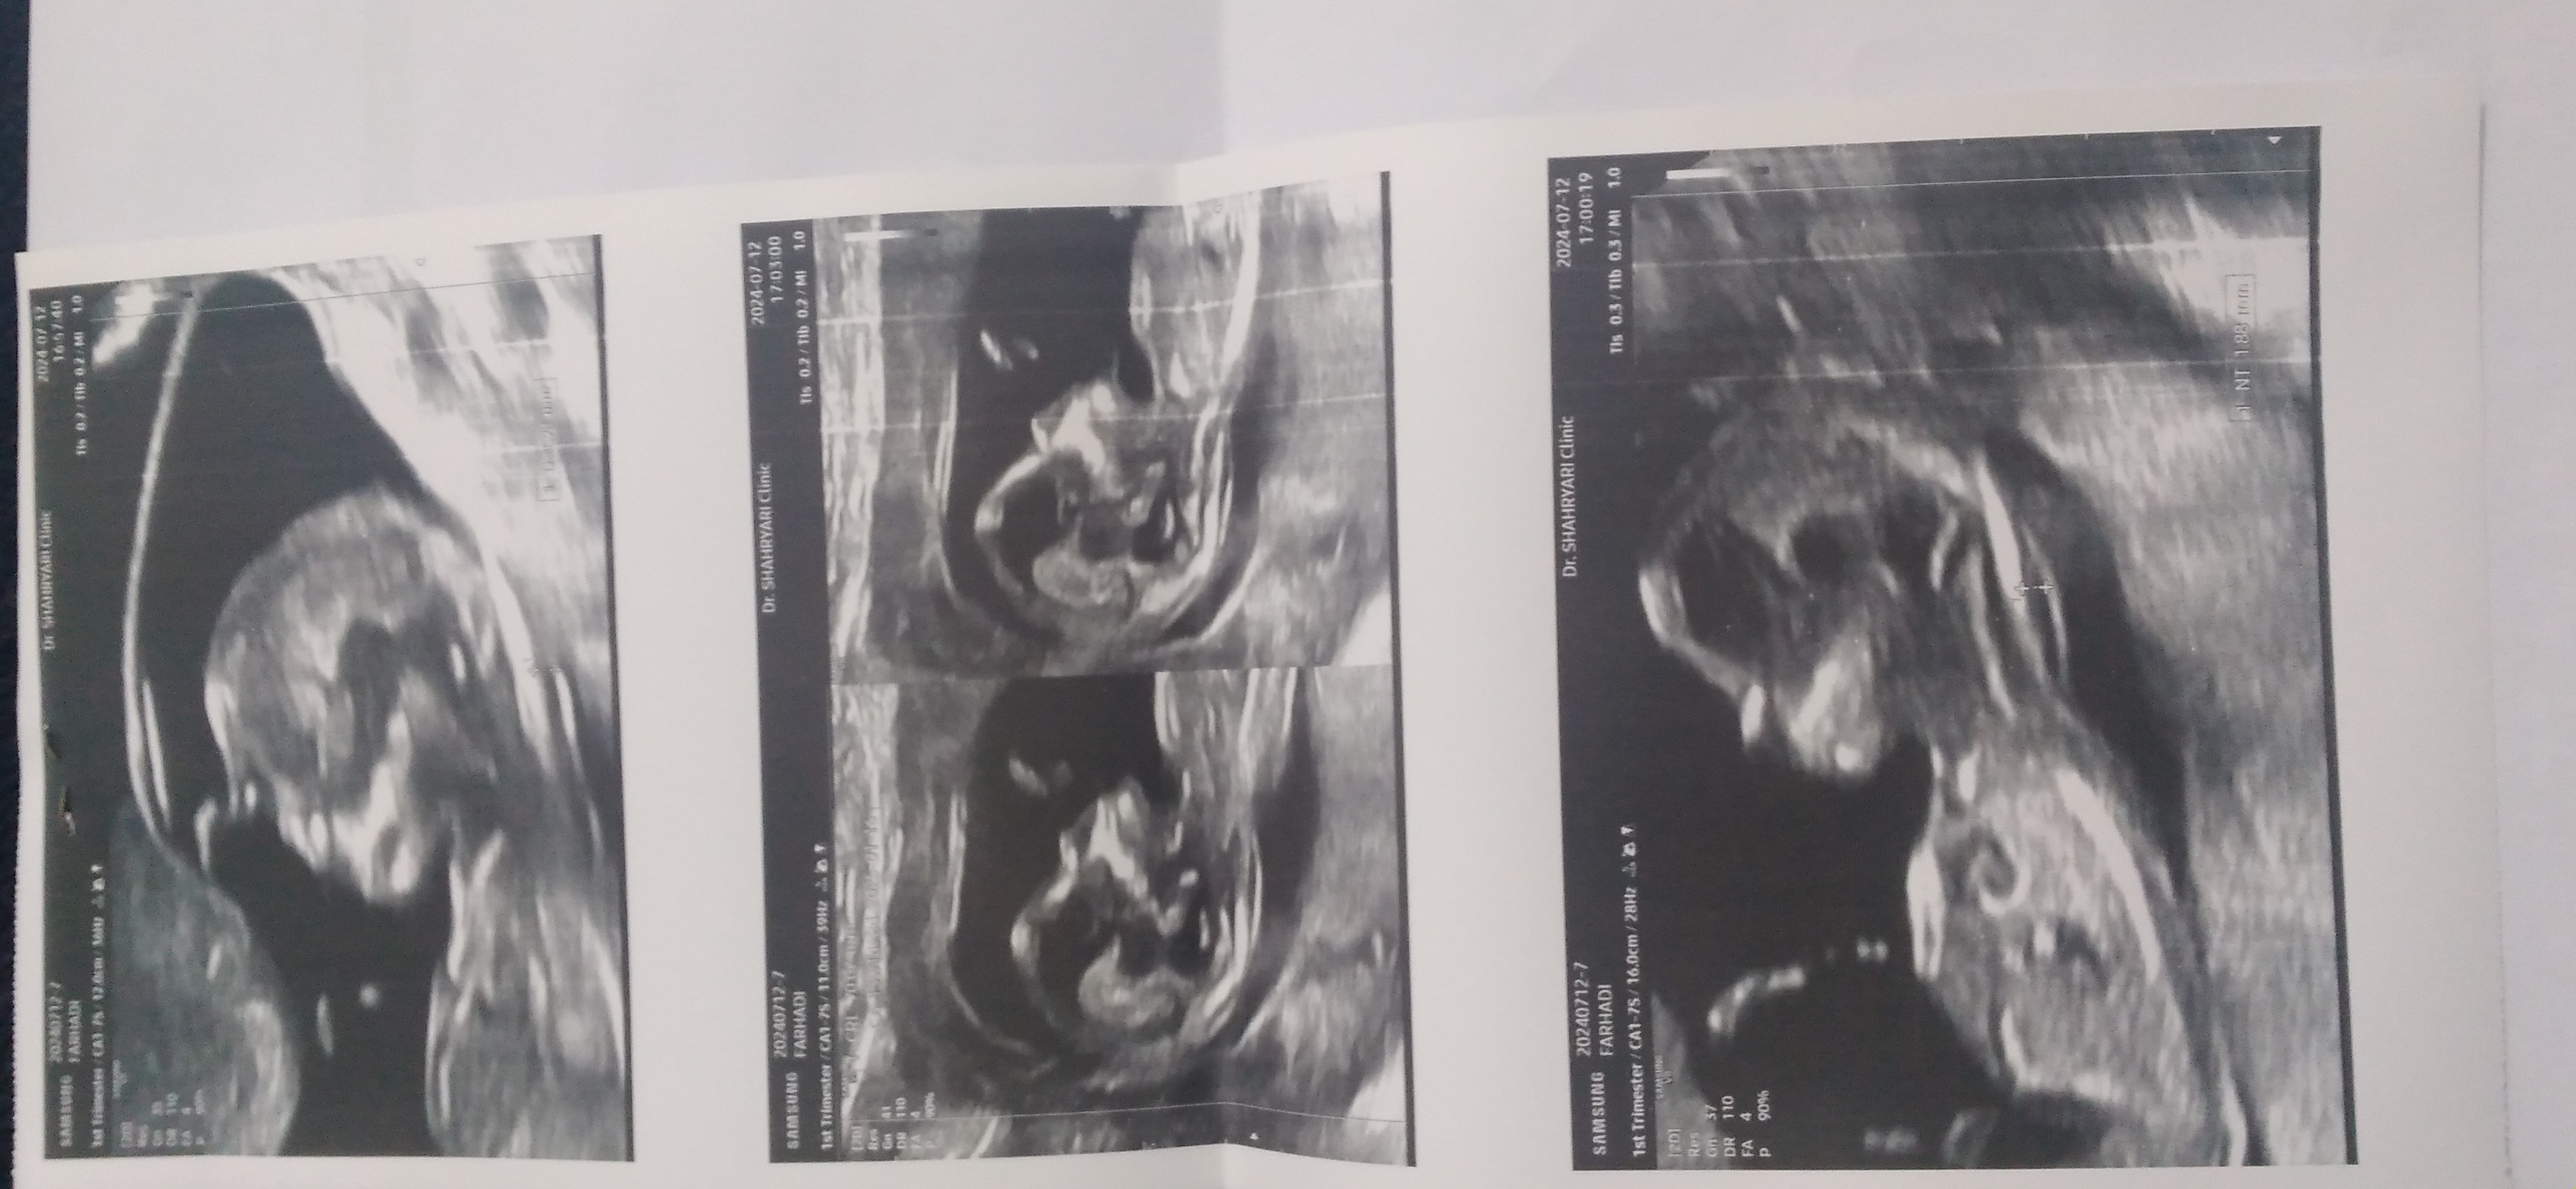

اهان ممنون دکترگفت معلوم نیست دوهفته دیگه بیاولی همون میخوام انومالی برمشمام دوقلودارین؟